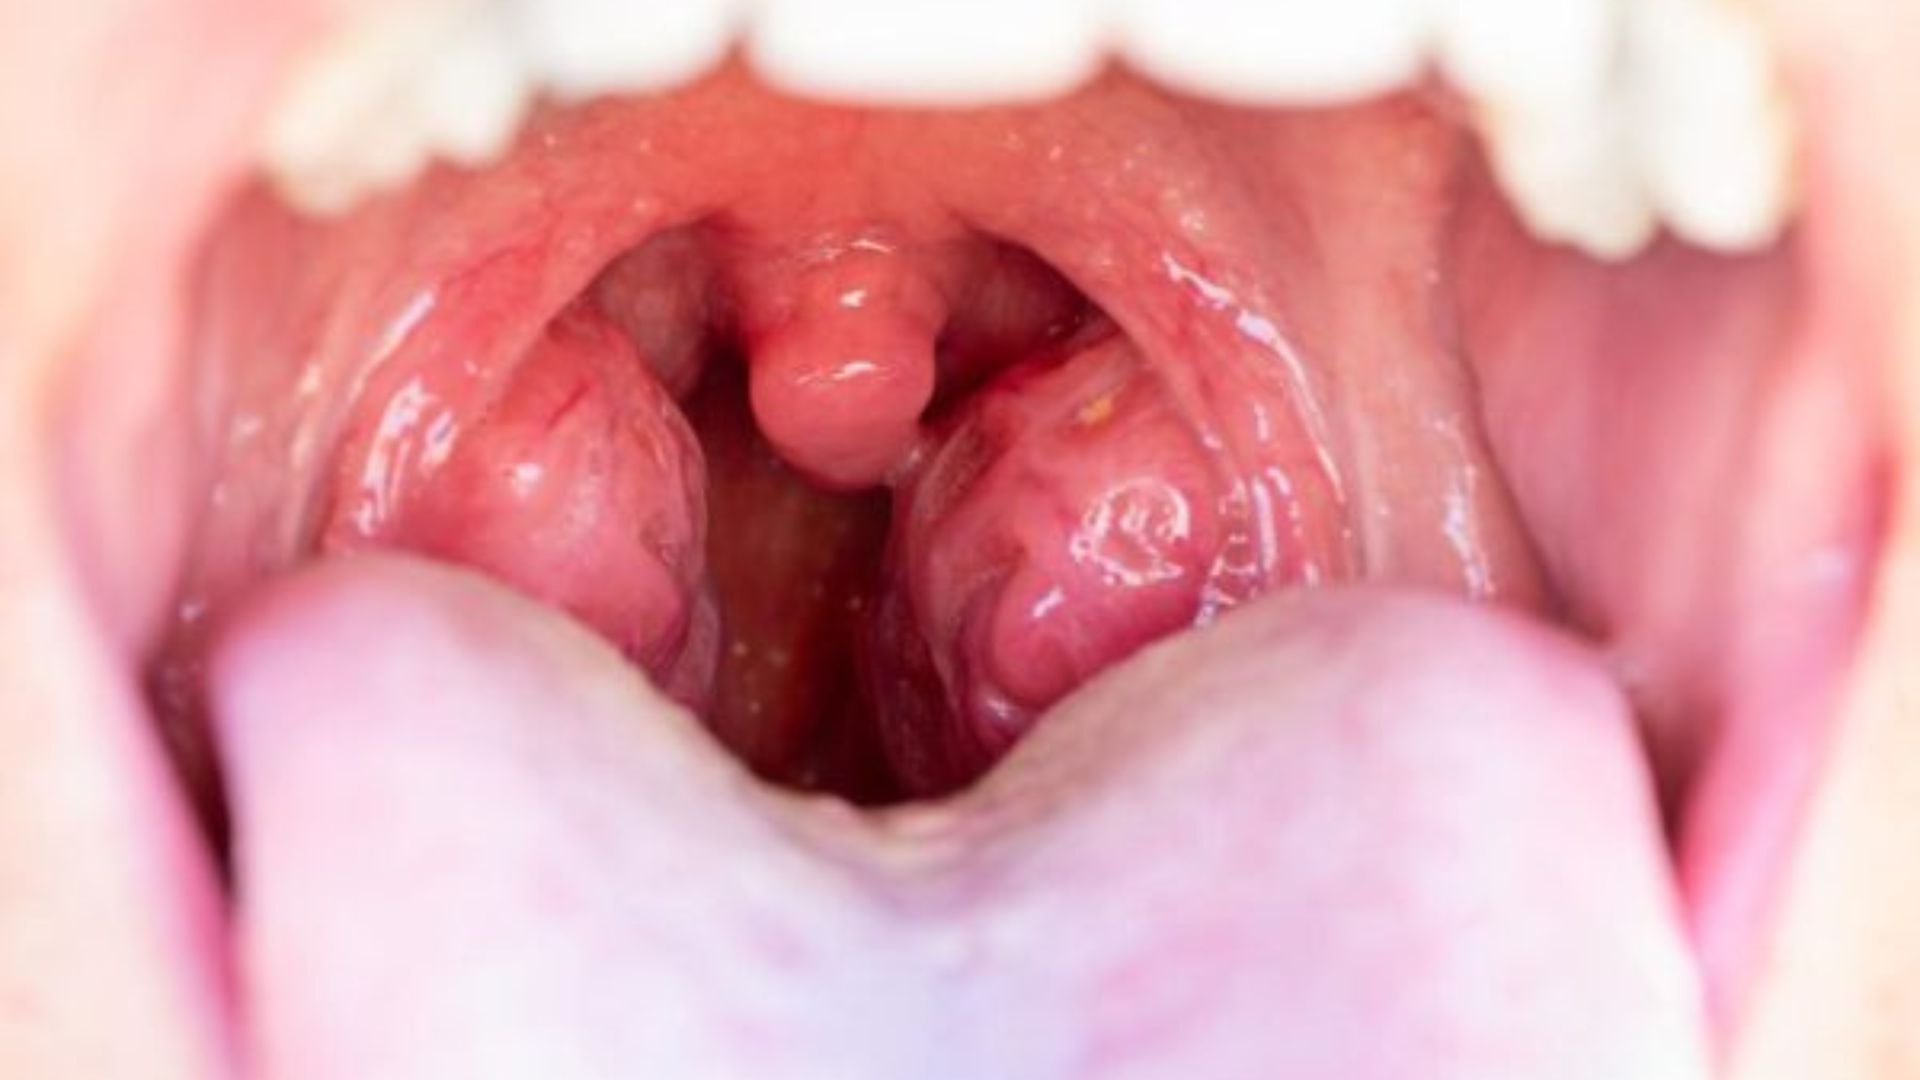

Radang amandel adalah kondisi ketika amandel (tonsil) terjadi inflamasi atau peradangan akibat infeksi. Kondisi ini dalam istilah medis juga sering disebut sebagai tonsilitis.

Amandel merupakan baris pertahanan terdepan tubuh kita dalam melawan penyakit. Terletak di belakang tenggorokan, tonsil berisi sekumpulan kelenjar getah bening yang akan memproduksi sel darah putih untuk membantu tubuh dalam melawan infeksi.

- Amandel terlihat bengkak dan memerah

- Amandel memiliki titik putih atau kekuningan